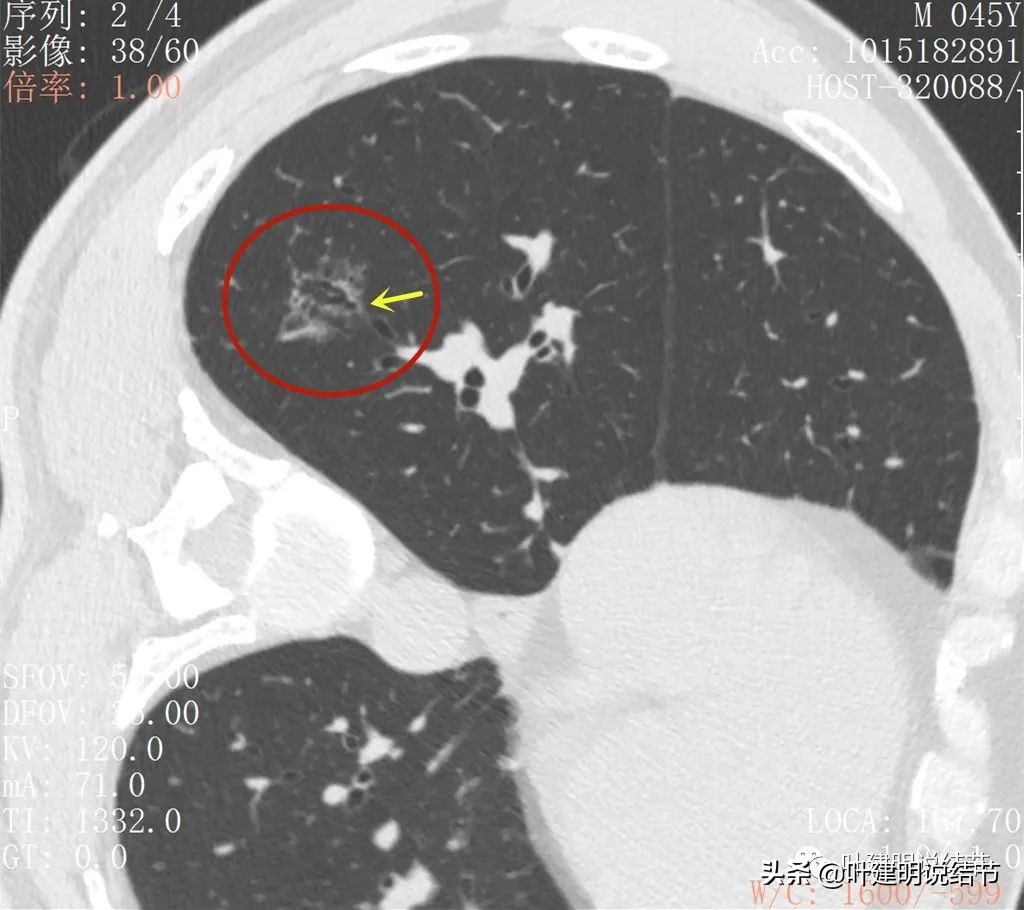

再来看薄层扫描:

病灶感觉很散在,但内部有扩张的细支气管(黄色箭头)、边缘略显不清(绿色箭头),部分有偏实性(粉色箭头)。

边缘血管异常增粗(桔色箭头),边缘显糊(绿色箭头),细支气管扩张(黄色箭头)